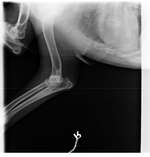

mein Rüde (13 Monate, nicht kastriert) hat, sobald er seinen Penis ausschachtet, vorne wie eine gelbliche Beule. Ich glaube, dass diese unter der Haut liegt, er verliert keine Flüssigkeit und auch kein Smegma.

Wir sind deswegen gestern beim Tierarzt gewesen, leider hat dort der k ...